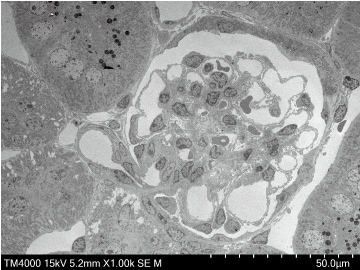

样品:老鼠肾脏

加速电压:15 kV

观察信号: STEM 图像

放大倍率:1000倍